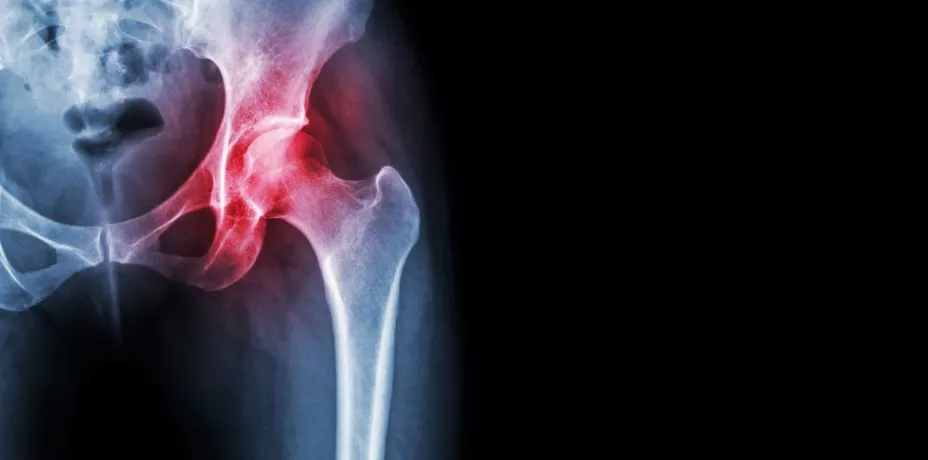

Explicó que, si “las personas vienen en diferentes tamaños y formas, el reemplazo de cadera tendría que ser igual. Cuando se hace un reemplazo de cadera personalizado, se realiza una tomografía computarizada de la pelvis y el área de la cadera, y a partir de esa tomografía computarizada se desarrolla un modelo 3D completo del paciente y a través de un software se diseña el reemplazo de cadera que mejor se adapte y por ende el paciente esté más cómodo.”

De acuerdo con Conformis, empresa creadora de este sistema, la tomografía computarizada de cada paciente ayuda a tener un modelo tridimensional y estas medidas se transforman en un plan quirúrgico preoperatorio completo e individualizado que se entrega al cirujano mucho antes de la operación.